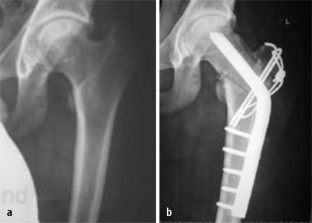

Abb. 2